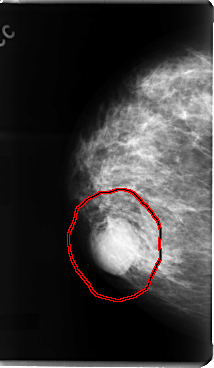

FILE: C_0076_1.RIGHT_MLO.OVERLAY

TOTAL_ABNORMALITIES 1

ABNORMALITY 1

LESION_TYPE MASS SHAPE LOBULATED MARGINS MICROLOBULATED

ASSESSMENT 4

SUBTLETY 5

PATHOLOGY MALIGNANT

TOTAL_OUTLINES 1

BOUNDARY